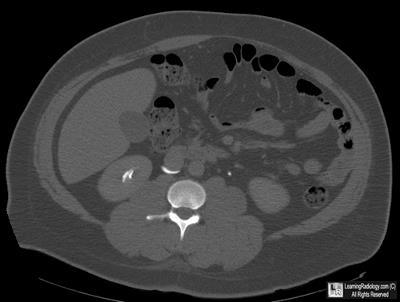

Additional Images-Axial CT image of abdomen

Axial CT image of abdomen

3. Retrocaval ureter

RetroCaval Ureter

- Also known as “circumcaval ureter”

- Abnormality in embryogenesis of IVC

- Results from abnormal persistence of right subcardinal vein positioned ventral to ureter in the definitive IVC

- Developing right ureter courses behind and medial to the IVC